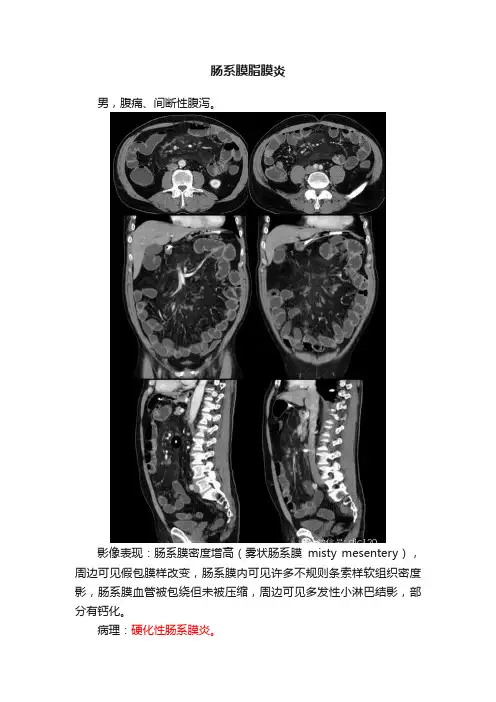

肠系膜脂膜炎男,腹痛、间断性腹泻。

影像表现:肠系膜密度增高(雾状肠系膜misty mesentery),周边可见假包膜样改变,肠系膜内可见许多不规则条索样软组织密度影,肠系膜血管被包绕但未被压缩,周边可见多发性小淋巴结影,部分有钙化。

病理:硬化性肠系膜炎。